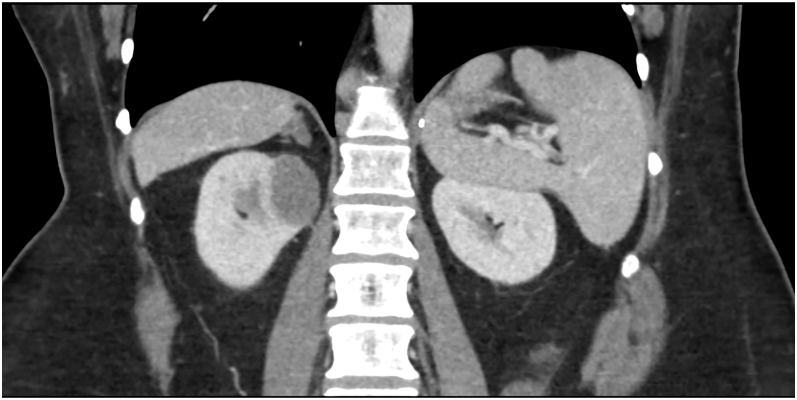

Summary: Hereditary leiomyomatosis and renal cell cancer (HLRCC) is an autosomal dominant condition characterized by multiple cutaneous and uterine leiomyomas and renal cell cancer (RCC). HLRCC is caused by germline pathogenic/likely pathogenic (P/LP) variants in the fumarate hydratase (FH) gene on chromosome 1q42.3, encoding the mitochondrial enzyme responsible for the conversion of fumarate to malate in the Krebs cycle. 0.6-3.1% of individuals with pheochromocytoma/paraganglioma (PCC/PGL) carry a germline variant in the FH gene. Most of these patients have no personal or family history of HLRCC-associated manifestations, but some of them do. We described a female-to-male transgender with HLRCC who presented with large symptomatic uterine leiomyomas in the third decade of life and was diagnosed with a PCC 19 years after hysterectomy and with cutaneous leiomyomas and an aggressive form of RCC in the sixth decade of life. With the publication of this case and the review of the existent literature, and until more information becomes available, we would like to emphasize that clinicians should be aware of the possible connection between HLRCC and PCC/PGL, that genetic testing for susceptibly genes for PCC/PGL should include the FH gene and finally that patients with HLRCC should be screened for PCC/PGL.

Learning points: HLRCC, an autosomal dominant condition caused by germline P/LP variants in the fumarate hydratase (FH) gene, is characterized by multiple cutaneous and uterine leiomyomas and RCC.0.6-3.1% of individuals with PCC/PGL carry a germline P/LP variant in the FH gene.Most of these patients have no personal or family history of HLRCC-associated manifestations, but some of them do.Preliminary evidence suggests that genetic testing for susceptibly genes for PCC/PGL should include the FH gene and that patients with HLRCC should be screened for PCC/PGL.Until more information becomes available, we suggest doing a full history, physical, family history, and screen for HLRCC-associated manifestations when there is an FH variant.Screening for PCC/PGL in patients with HLRCC could potentially include a baseline whole-body MRI and plasma fractionated metanephrines.